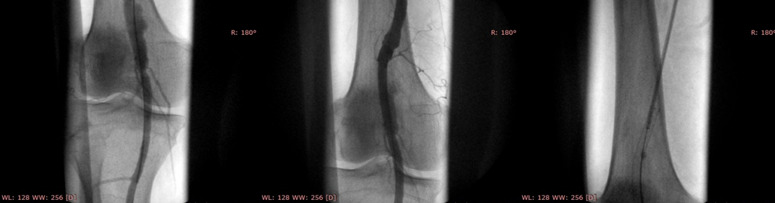

E’ salvo l’arto inferiore del paziente grazie ad un delicato intervento di esclusione endovascolare di…